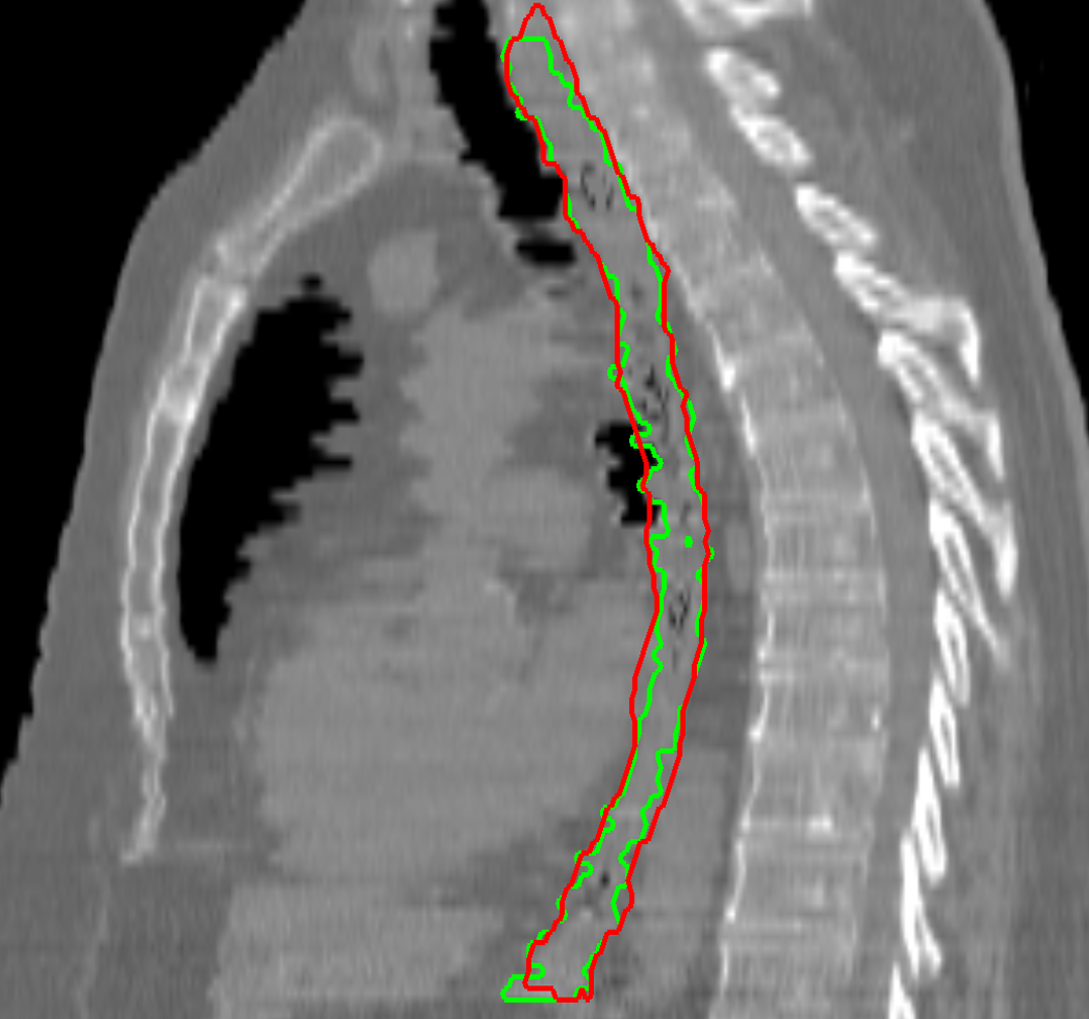

Visual results of our algorithm compared to the reference contour for 6 cases in axial and sagittal view are depicted in Fig. 5. From the sagittal views it can be observed that manual contours are not as smooth as the automatic contours, which could be due to the breathing artifacts. The use of convolutions and post-processing in 3D aids at processing information of the 3D context through several slices, which is reflected in the smoother automatic contours shown in these images. On the other hand, from the axial views we can realize that, despite of the similarity with respect to neighboring tissues, and heterogeneity of the inner region of the esophagus, our automatic system provides contours that are comparable with the reference standard.

Refer to caption a) clinical case 09 sagittal view Refer to caption b) clinical case 13 sagittal view Refer to caption c) clinical case 20 sagittal view

Refer to caption d) clinical case 09 axial view Refer to caption e) clinical case 13 axial view Refer to caption f) clinical case 20 axial view

Refer to caption g) public case 01 sagittal view Refer to caption h) public case 12 sagittal view Refer to caption i) public case 24 sagittal view

Refer to caption j) public case 01 axial view Refer to caption k) public case 12 axial view Refer to caption l) public case 24 axial view

Figure 5: Contouring results for 6 cases in different views. The green line indicates the reference standard, the red line depicts the contour generated by the proposed algorithm.